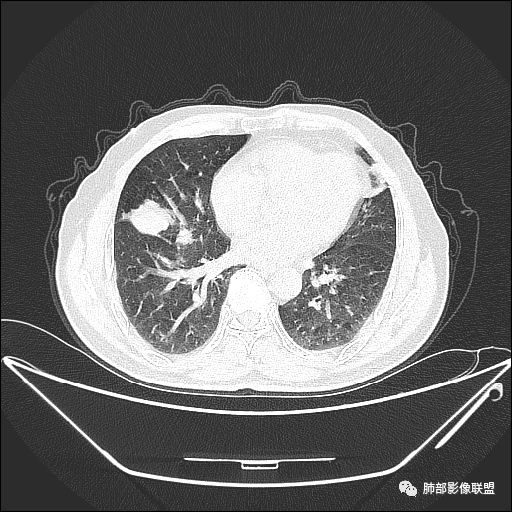

入院CT

老年男性,亚急性病程,咳嗽咳痰。右肺中叶团片影,外朝内分布,大部分边界清楚平直,内侧支气管进入,团片影见低密度坏死区,强化明显,延迟强化,血管破坏不明显,符合爬行征5个特点:

1.肺外周生长。

2.外侧部分体积大于内侧。

3.病变最大径与肺的纵轴及水平面任何一条轴线不平行。

4.病变内侧支气管通畅。

5.病变区域肺容积无缩小。

双侧肺门及纵隔淋巴肿大并可见钙化。考虑结核,但部分边缘膨隆,肿瘤待排。

主病灶在中叶,但是左肺舌段叶有条索影,陈旧病变。蓝色箭头支气管受压,是淋巴结肿大

主病灶在中叶,但是还有结节状病变在下叶

叶间裂推移方向

虽然是一个大的病灶,但是周围是比较散

边缘还有多发小灶

淋巴结肿大,钙化。

但是钙化,密度高,没有融合,平扫没有坏死

病灶明显平直,中央是粘液栓,低密度,分界清楚